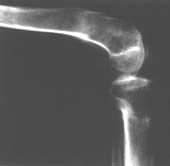

> Пациент В. 53 лет, травма в феврале 2009. ДЗ. Открытый оскольчатый перелом нижней трети голени. При боли поступлении выполено ПХО, аппарат Илизарова. В последующем проводили ВХО, резекция костных отломков, укорочение 6 см, рана зажила. Была выполнена остеотомия большеберцовой кости в проксимальном отделе, резекция. Производилось тракция.

> На последних рентгенограммах выявлено, что одновременно с "выращиванием" регенерата произошло низведение надколенника  на длину выращенного регенерата.

> Клинически: активное разгибание сохранено, объем движений в колене 180-110 градусов.  Черными стрелками обозначен верхний край надколенника с одной и с другой стороны. Красная стрелка обозначает пальпируемую связку надколенника.

> Причина - остеотомия выше места прикрепления связки надколенника.